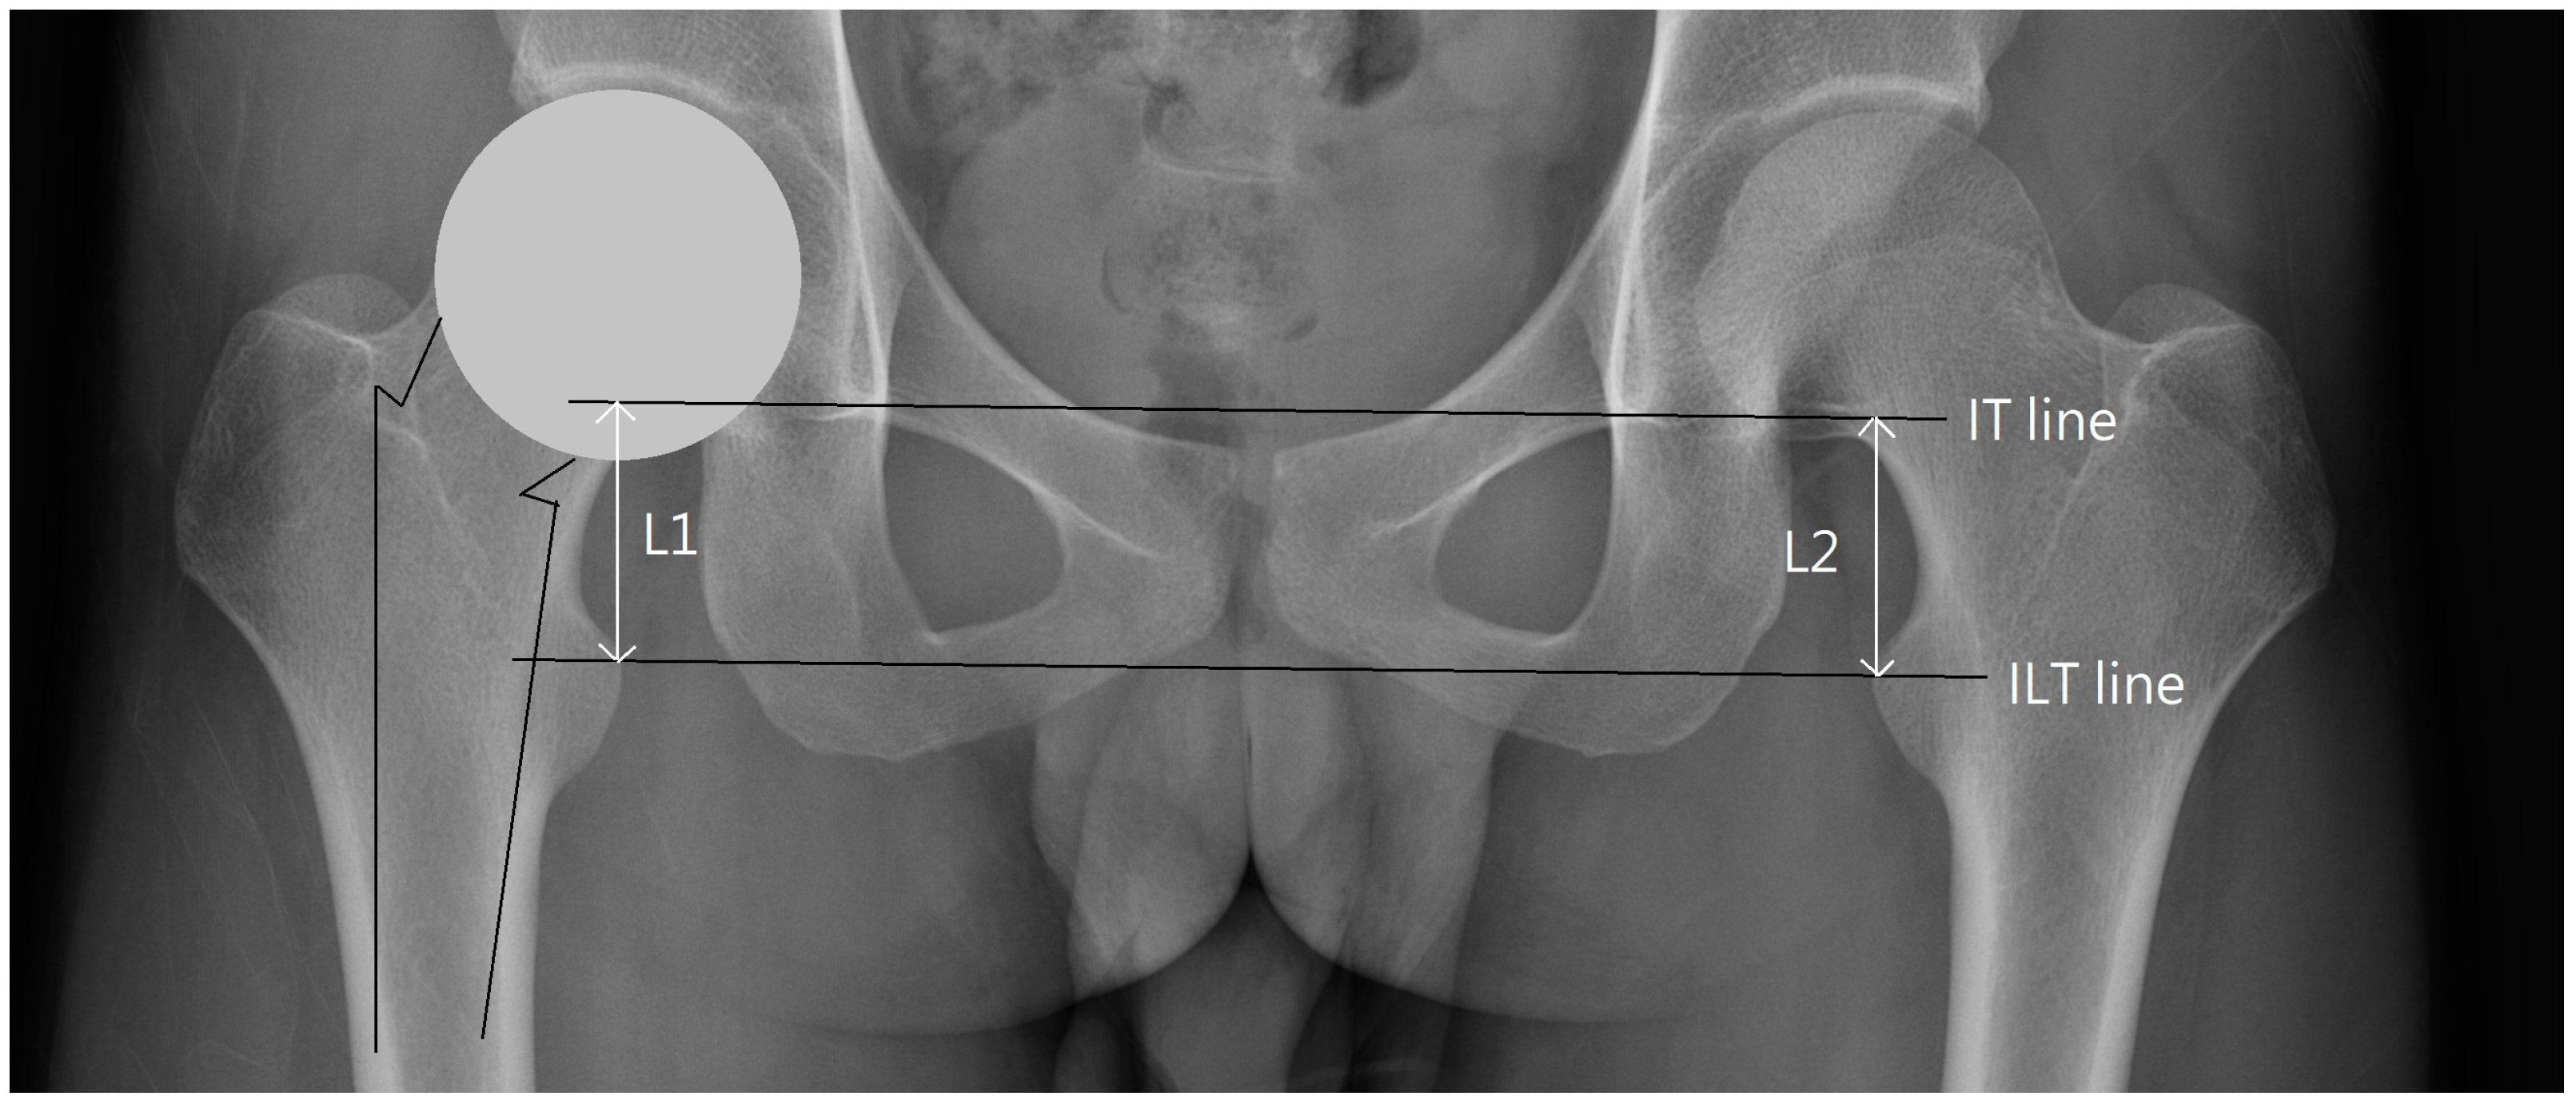

From www.researchgate.net

Radiological assessment of hip geometry. Download Scientific Diagram Hip Replacement Evaluation The main steps of total hip replacement surgery are: This overview focusses on the normal findings and complications of. The damaged hip joint is taken apart. The top end of the thigh. These guidelines are designed to guide the physiotherapist when treating patients following a total hip replacement. Radiography is the primary imaging method for the evaluation of total hip. Hip Replacement Evaluation.

(PDF) Leg and Femoral Neck Length Evaluation Using an Anterior Capsule Hip Replacement Evaluation Radiography is the primary imaging method for the evaluation of total hip arthroplasty. The surgeon makes a cut, or a number of cuts, in the back or side of your hip. Ask if the patient has had a hip replacement (if so internal rotation, adduction and flexion greater than 90° should be avoided due to the risk of joint dislocation).. Hip Replacement Evaluation.